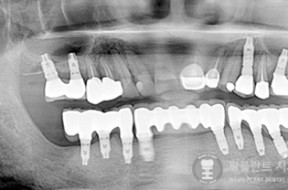

전후사례